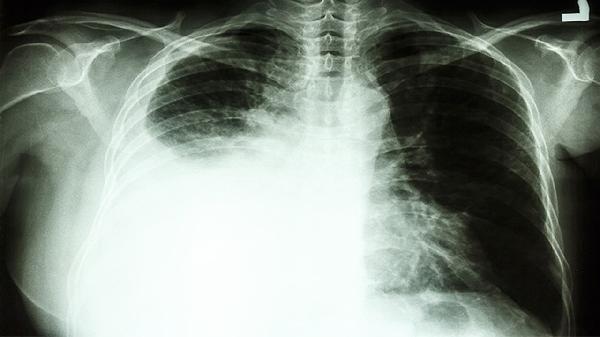

当肿瘤阻塞气道或引发胸腔积液时,可能出现进行性加重的气促,初期仅在活动后明显。伴随哮鸣音或呼吸音减弱时提示气道狭窄。肺功能检查可评估通气障碍程度,胸腔穿刺能明确积液性质。

肿瘤导致支气管阻塞易引发阻塞性肺炎,表现为同一部位反复发生肺炎,抗感染治疗效果有限。常见发热、脓痰等感染症状。需通过增强CT判断肺部实变是否由肿瘤引起,必要时进行经皮肺穿刺活检。